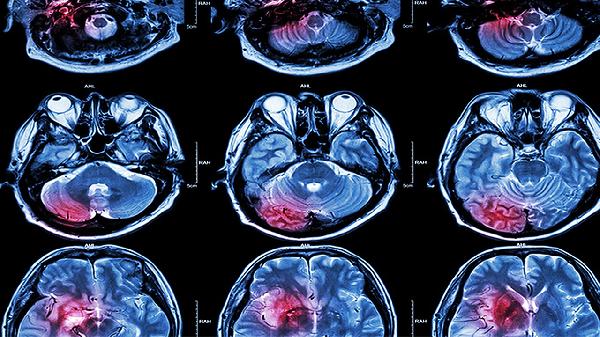

每6-12个月需进行脑血管造影或磁共振血管成像检查,评估侧支循环代偿情况。儿童患者应增加随访频率,青春期前后血管病变可能快速进展。检查发现新发血管狭窄或动脉瘤需考虑手术干预。